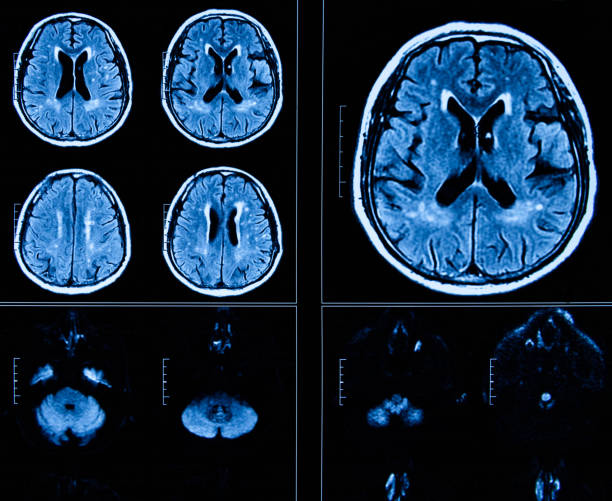

istockphoto 1196916327 612x612 1

MRI scan human head Tomography